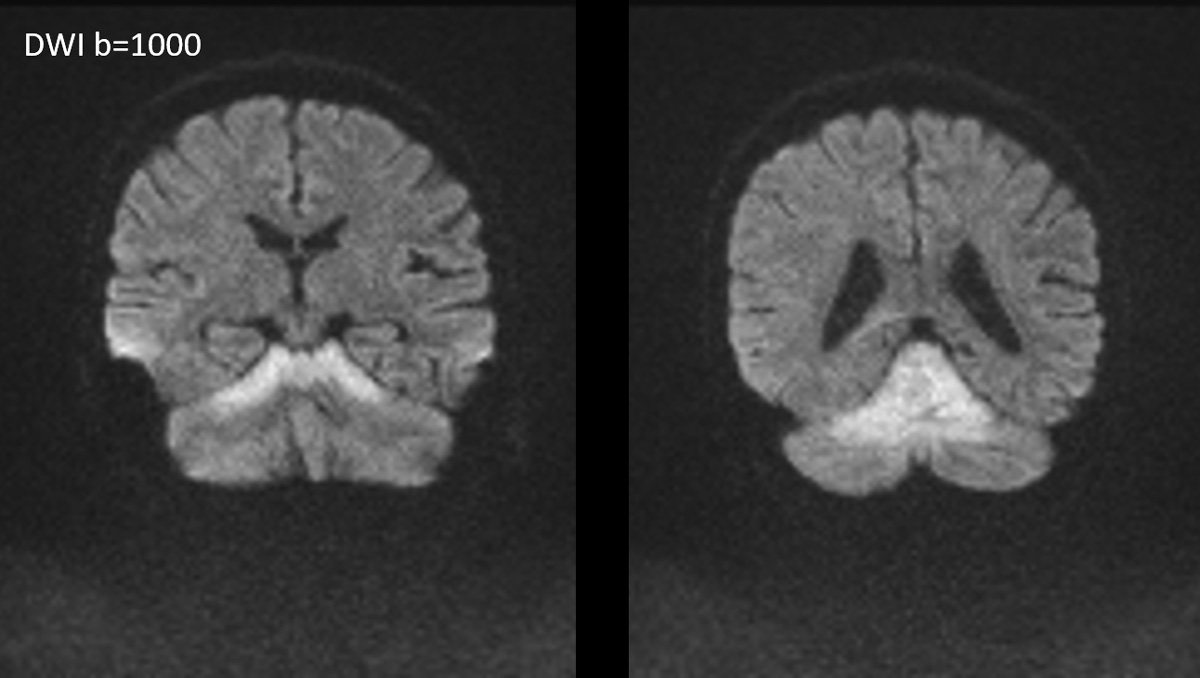

症例1:28歳男性

- 4か月ほど前から歩行時の息切れあり、1か月前から下肢の疼痛が出現、1週間前からはベッド上で生活していた。

- 3日前から呂律が緩慢となり、増悪したため、父親が救急要請。